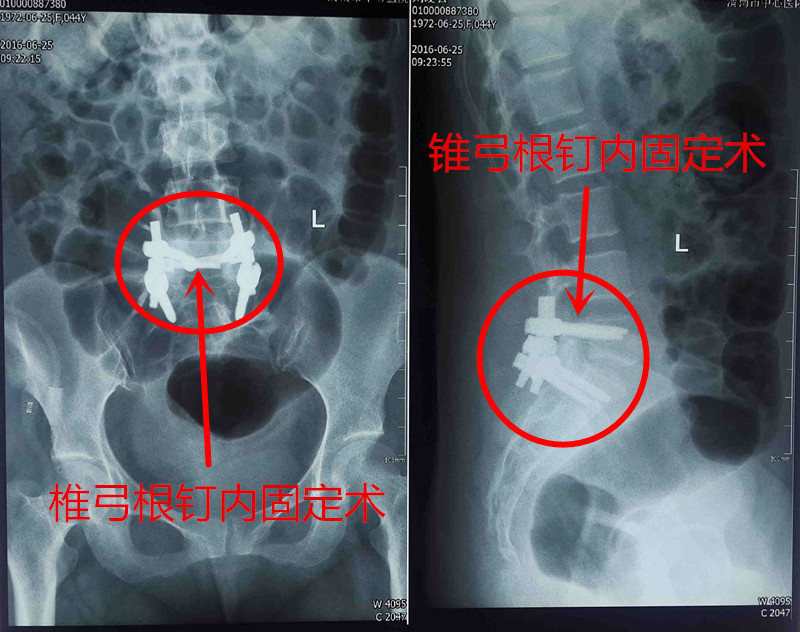

住院后经过查体,可见患者骶尾部皮肤肿胀,皮肤感觉稍有麻木。腰骶部活动正常,双下肢肌力、感觉正常,磁共振提示:腰5骶1平面椎管内占位病变。经全面检查后,诊断为椎管内肿瘤,非手术治疗无效,且患者骶尾部疼痛麻木症状重,影响患者生活及工作,已达到手术指征。在骨一科主任、主任医师翁润民主持下,雷广宇副主任医师、杨杰副主任医师和王旭阳主治医师等多次研讨手术方案,决定采取手术治疗。

经过充分的术前准备,6月20日,在全身麻醉下,由翁润民主任主刀,在雷广宇、杨杰副主任医师等协助下,行椎管肿瘤切除术、椎体植骨融合内固定术。患者的肿瘤与马尾神经粘连,手术难度较大,稍不注意可能导致患者瘫痪。经过2个多小时的努力,终于成功将肿瘤予以摘除。术后患者生命体征平稳,恢复良好。